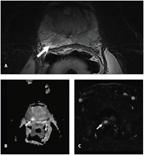

FIGURE

Multiparametric Magnetic Resonance Imaging (MRI) of a Highly Suspicious Focus (arrows) in the Posterior Medial and Lateral Peripheral Zone of the Prostate

One of the more important areas of innovation to emerge recently is the evolution of prostate imaging techniques. In the past, we relied almost exclusively on blind sampling of the prostate to evaluate and stage localized PCa. At present, several imaging techniques have been proposed that potentially allow for identification of the malignant foci within the gland. These methodologies include ultrasound-based techniques such as elastography, contrast-enhanced ultrasound, HistoScanning™, and acoustic radiation force impulse imaging.[19-21] In addition, MRI, specifically with the use of additional functional sequences (diffusion-weighted, contrast-enhanced spectroscopy), is considered to be the most solid imaging platform for localized PCa.[21,22] The Figure depicts MRI revealing a highly suspicious focus in the posterior medial and lateral peripheral zone that was pathologically confirmed to be a Gleason 7, organ-confined PCa.